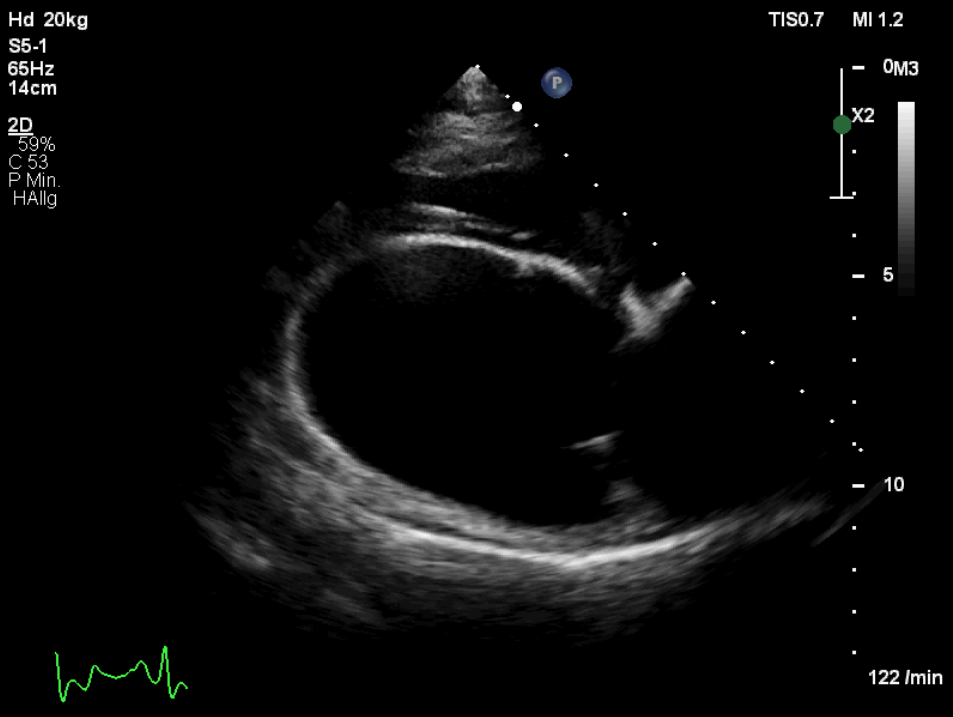

Die klinische Untersuchung war bis auf vereinzelte Pulsdefizite und einen phasenweise unregelmäßigen Herzschlag unauffällig. Zur vollständigen kardiologischen Abklärung wurden eine Echokardiographie in rechter und linker Seitenlage (Abb. 1), ein Kurzzeit-EKG während des Ultraschalls und ein 24-Stunden-Holter-EKG durchgeführt.

Für die echokardiographische Untersuchung ist i. d. R. keine Sedierung notwendig. An einer kleinen Stelle an der Brustwand werden die Haare geschoren, was aber je nach Haardichte und -beschaffenheit nicht immer notwendig ist. Bei Bubi zeigte sich im Herzultraschall das typische Bild der Dobermann-Kardiomyopathie: Eine Volumenüberladung des linken Ventrikels und des linken Atriums war auffällig, genauso wie eine schlechte systolische Funktion (Abb. 2 und 3). Diese Volumenüberladung führte bereits zu einer geringgradigen sekundären Mitralklappeninsuffizienz.